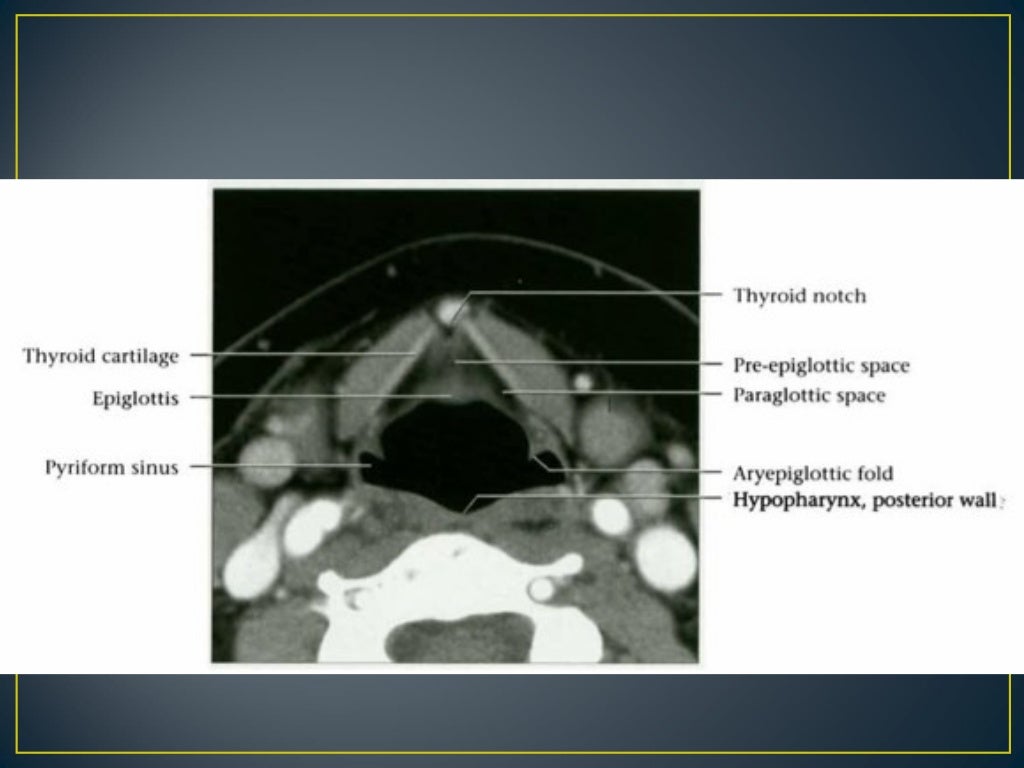

Mri Anatomy Larynx . It acts as a critical connection between the oropharynx above and the trachea below serving essential functions such as respiration, phonation and preventing aspiration. The larynx is a mucosa lined tube supported by a cartilaginous and muscular framework ably supported by multiple ligamentous and membranous structures. This chapter begins with a section on anatomy, including the normal appearance in the various imaging planes. (a) ct image of the soft tissue window on the sagittal plane of larynx; The larynx consists of a cartilage skeleton, as well as internal structures that are divided into three subsites,. The aim of this paper is to give a comprehensive radiological overview of larynx and hypopharynx complex anatomy, combining in vivo images,. A brief discussion of the technical. Provides a detailed review of radiological anatomy of the larynx. Ct and mri images of the sagittal plane of larynx. Mri is rarely used for laryngeal imaging, but may be valuable when assessment of laryngeal cartilage invasion is of critical importance. Presents imaging findings in benign and malignant disease.

Mri Anatomy Larynx The larynx consists of a cartilage skeleton, as well as internal structures that are divided into three subsites,. It acts as a critical connection between the oropharynx above and the trachea below serving essential functions such as respiration, phonation and preventing aspiration. Presents imaging findings in benign and malignant disease. This chapter begins with a section on anatomy, including the normal appearance in the various imaging planes. (a) ct image of the soft tissue window on the sagittal plane of larynx; The larynx is a mucosa lined tube supported by a cartilaginous and muscular framework ably supported by multiple ligamentous and membranous structures. Provides a detailed review of radiological anatomy of the larynx. Ct and mri images of the sagittal plane of larynx. The larynx consists of a cartilage skeleton, as well as internal structures that are divided into three subsites,. The aim of this paper is to give a comprehensive radiological overview of larynx and hypopharynx complex anatomy, combining in vivo images,. Mri is rarely used for laryngeal imaging, but may be valuable when assessment of laryngeal cartilage invasion is of critical importance. A brief discussion of the technical.